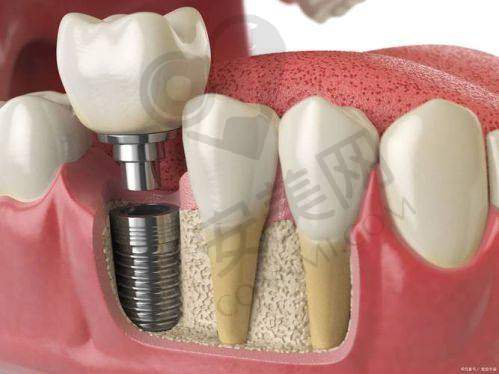

创英种植牙是一种精良的种植牙系统。它采用了高品质的种植材料,具有良好的生物相容性,能够与人体牙槽骨更好地结合,提高种植成功几率。创英种植牙的设计科学合理,模拟了天然牙齿的形态和结构,不仅在外观上与真牙几乎无差别,而且在功能上也能够接近真牙,让患者能够正常咀嚼食物。此外,创英种植牙的使用寿命较长,能够为患者提供长期稳定的牙齿修复成效。

创英种植牙的手术过程一般分为几个步骤。首先,患者需要到柳州中瑞口腔进行全方面的口腔检查,包括口腔CT扫描等,以确定患者的口腔状况和牙槽骨条件。刘轩医生会根据检查结果制定详细的种植方案。然后,在局部麻醉下,医生会在患者的牙槽骨上制备一个合适的种植窝,将种植体植入其中。植入后,需要等待一段时间,让种植体与牙槽骨充分结合,这个过程通常需要几个月的时间。之后,医生会安装基台和牙冠,完成整个种植牙的修复过程。在整个手术过程中,刘轩医生会严格遵循无菌操作原则,确保手术的安心和成功。